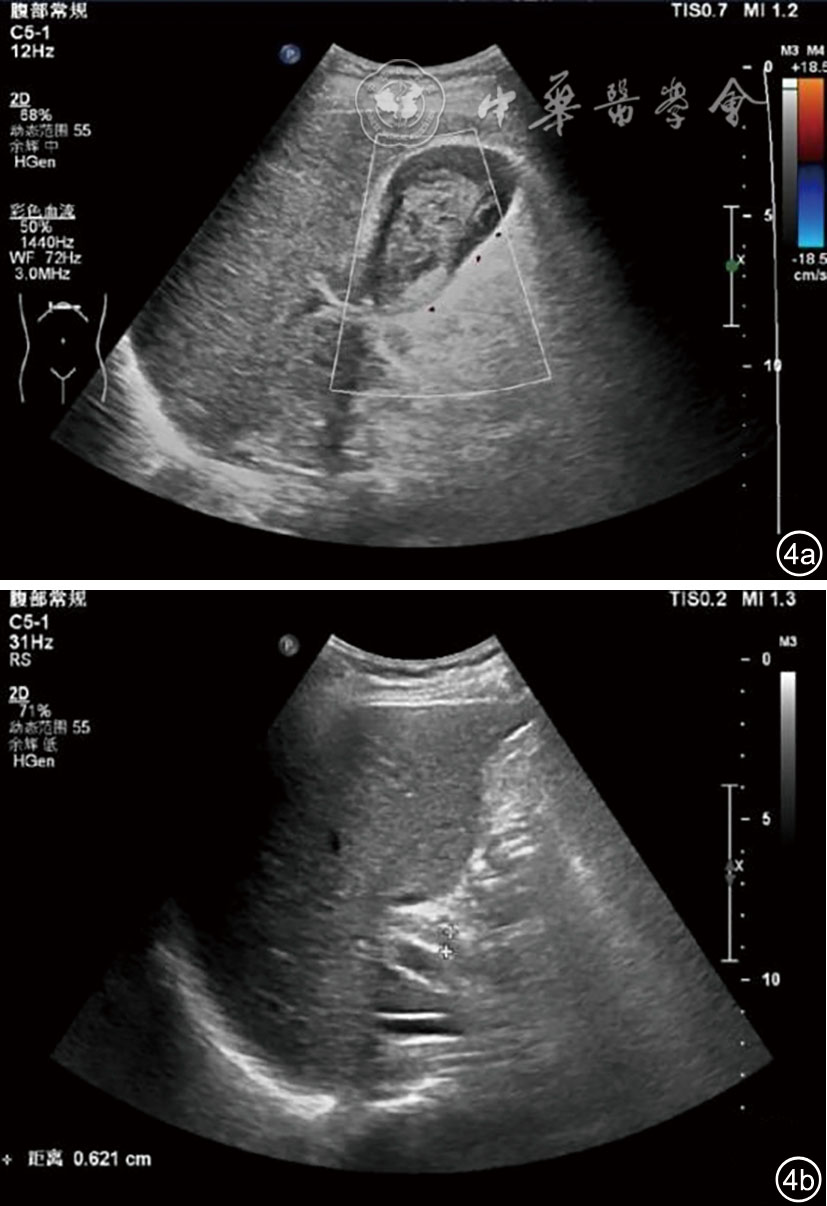

图4 经皮肝穿刺活检后腹部彩色多普勒超声图像。图a、b分别显示胆囊、胆总管内见高回声团块,境界清,形态欠规则,内回声欠均匀,彩色多普勒未见明显血流信号